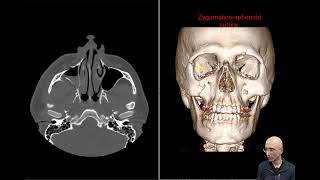

Zmc Fracture

14.621

1:23